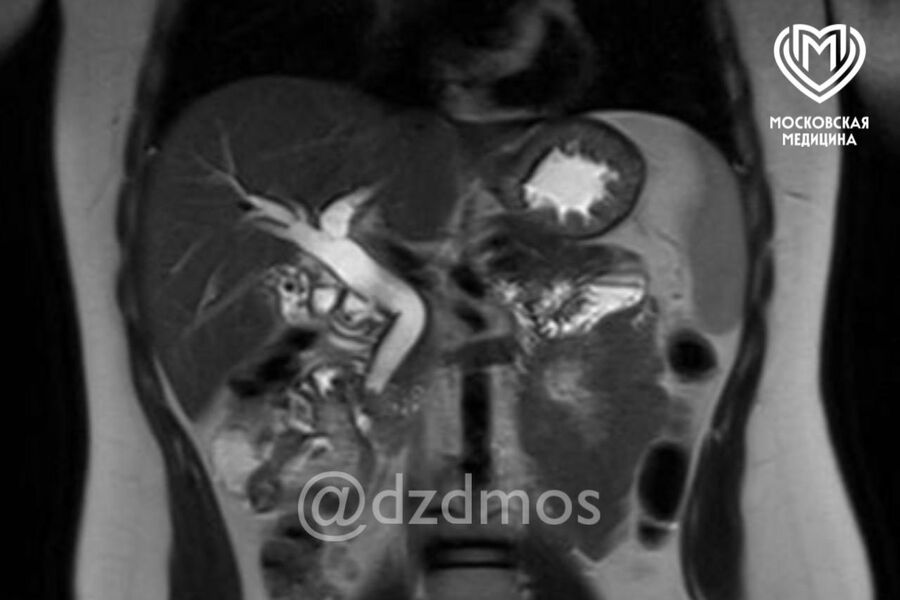

Врачи больницы имени Сперанского в Москве спасли девочку с огромным количеством камней в желчном пузыре. Об этом сообщили в пресс-службе департамента здравоохранения столицы.

Ребенок поступил в медицинское учреждение с болями в животе, рвотой и общей слабостью. Обследование показало, что в желчном пузыре ребенка скопилось огромное количество камней диаметром до 3 мм. Один из них перекрыл общий желчный проток, что угрожало жизни девочки.

Медики пояснили, что застрявшие в общем желчном протоке камни вызывают нарушение оттока желчи из печени — это приводит к развитию желтухи, начинает страдать печень, как и в случае с юной пациенткой. В тяжелых формах, как отметили специалисты, может развиться воспаление поджелудочной железы.

«Ребенку сделали эндоскопическую папиллосфинктеротомию: специальным аппаратом рассекли сосочек, впадающий в желчный проток, расширили его мышечное кольцо и извлекли камень. Вторым этапом удалили желчный пузырь, полностью забитый камнями», — рассказали в пресс-службе депздрава.